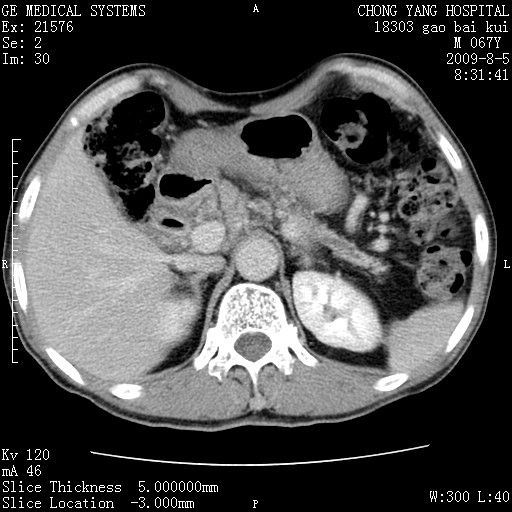

这个也过了,考虑胰腺钩突癌或壶腹癌,不除外胰管粘液乳头瘤伴胰管扩张,肝内胆管积气.

1)考虑胰头癌或壶腹癌并胰管扩张。2)肝外胆管扩张、积气,胆囊影未见;考虑术后改变。3)胃壁增厚?建议必要时行胃镜检查。

虑胰腺钩突癌或壶腹癌,不除外胰管粘液乳头瘤伴胰管扩张,肝内胆管积气.

考虑胰头癌并十二指肠受侵。